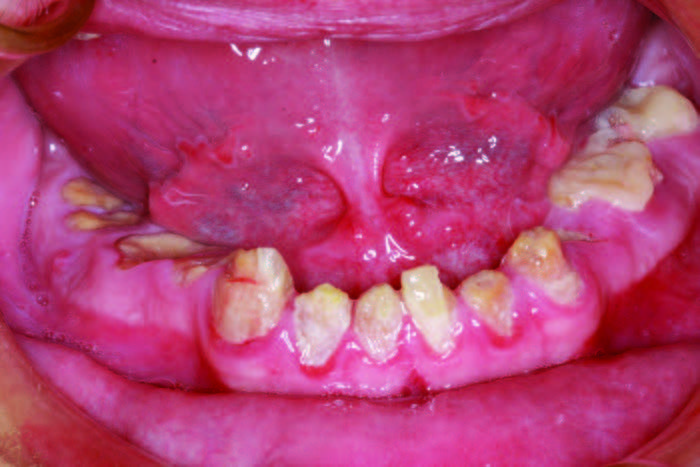

A 26-year-old male was diagnosed with hydrocephaly in utero. Hydrocephalus is a condition where there is an excessive accumulation of cerebral spinal fluid around the brain. Individuals affected with hydrocephalus often have impaired cognitive and physical development.[1,2] He was born into a loving family, but when his mother passed away from cancer, his father was unable to take care of a son with emotional and learning disabilities. This young man went on to have a terminal dentition due to poor oral habits. His grandparents stepped in and have been as supportive as possible, even while he has been living in a group home. They requested a treatment plan that would allow their grandson, whose teeth had been ravaged by soda, the dignity of having his smile replaced with implants. The patient’s Mountain Dew habit had destroyed his smile and self-esteem (Figure 1). The patient’s chronic soda habit with a lack of oversight at his group home led to gross generalized caries. Figure 2).